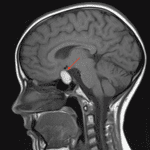

Indication: Headache, emesis

Findings

- Sellar mass with suprasellar extension uplifting the optic chiasm, with the normal pituitary gland not identified separate from the mass

- Diffuse intrinsic T1 hyperintensity with a rim of susceptibility artifact

- Heterogeneous T2/FLAIR intensity with a fluid-fluid level

- Otherwise, no evidence of acute intracranial abnormality

Diagnosis

- Pituitary apoplexy

T1 hyperintense sellar mass with suprasellar extension, most suggestive of hemorrhage into a preexisting pituitary adenoma. Recommend surgical evaluation.

Otherwise, no evidence of acute intracranial abnormality.